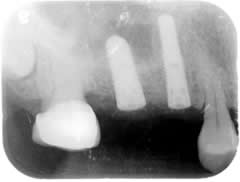

Sinus Lift:

The white line you see if the floor of the maxillary sinus. Above the white line is the sinus, air-filled sac. There is no bone in the sinus.

Extra bone graft is needed to lift the floor of the sinus. This procedure is called Sinus Lift.